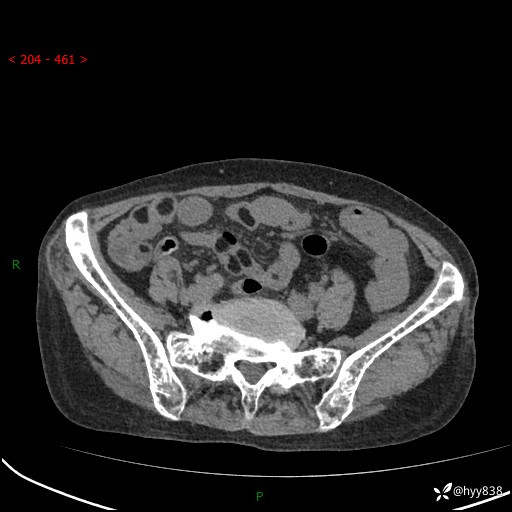

全腹部CT平扫